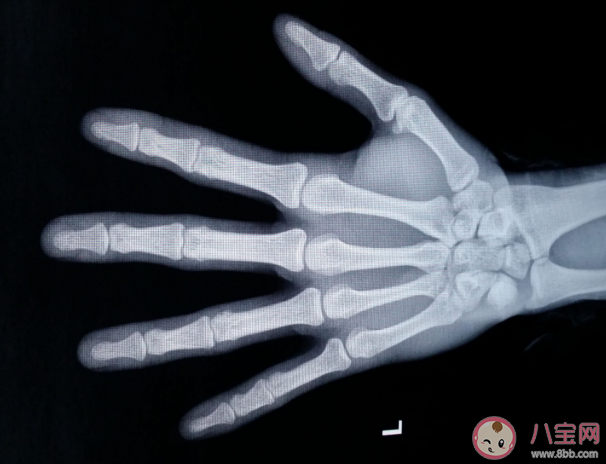

骨齡偏大意味著孩子長高的時間變短了,當骨齡明顯提前時,應及時就診,并不是所有骨齡偏大都需要治療,骨齡偏大原因是什么?下面八寶網小編就帶來介紹。

骨齡與實際年齡(簡稱年齡)之間的關系,用骨齡差來表明。骨齡差為年齡與骨齡之差。骨齡差為正數,代表骨齡落后于年齡;骨齡差為負數,則代表骨齡提前于年齡。通常將±2歲為骨齡差正常范圍,其中骨齡差在±1歲為正常。骨齡大于年齡1歲但不超過2歲為偏早;骨齡小于年齡1歲但不超過2歲為偏晚。如骨齡>年齡2歲, 認為骨齡異常提前;骨齡<年齡 2歲,認為骨齡異常落后。為了更好地評估生長發育狀況,骨齡結果要求精準、一致、穩定。